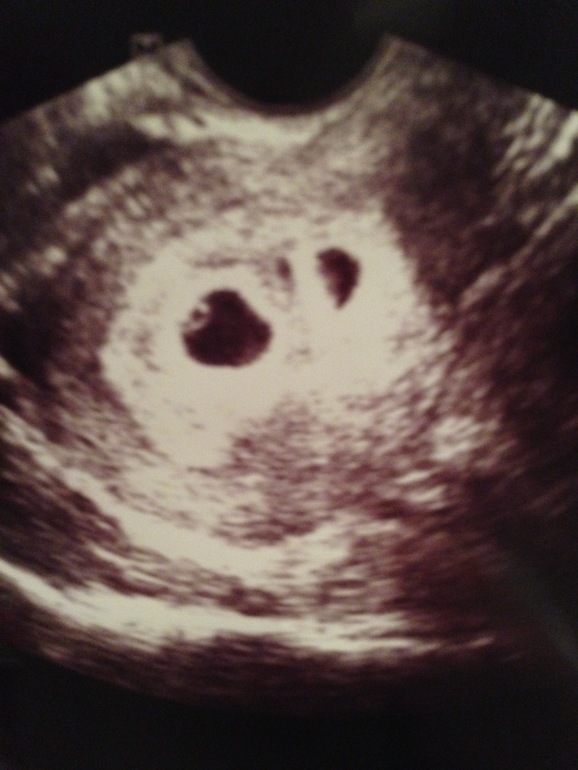

а вам акушерских или эмбриональных? у меня есть в 5 нед акушер или 3 нед эмбр

Обалдеть второй маленткий и все ок ?я почему спрашиваю у меня простотдва раза было два и второй очень мелкий и никогда он не выживал,замирал всегда(

у обоих было сердцебиение. но увы один потянул другого на свет божий(((

Ох извините,держитесь ((у меня до сердцебиения даже не доходило еще ,яйцо второе просто пустым оставалось(

Спасибки.у вас в облих желточный мешок был?второй маленький он догнал да?

Есть в 5 только